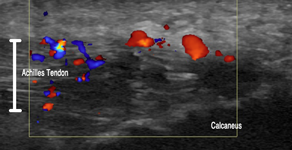

You can learn the skill and importance of using Musculoskeletal US to assist in grading, imaging (client feedback) and progressing treatment at Peter Esselbach's Rehabilitative Ultrasound Imaging - Level 1 and Rehabilitative Ultrasound Imaging - Level 2. Peter will also be presenting his Level 3 course in Perth for those with previous experience and wishing to enhance both their musculoskeletal and real time US skills.